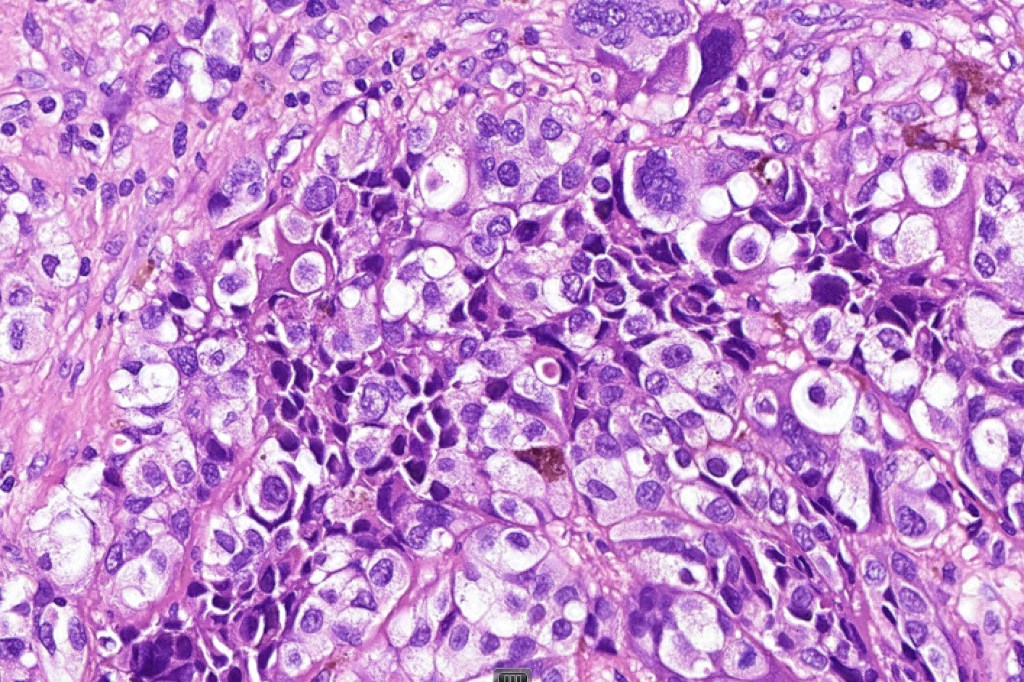

These are very rare variants of amelanotic or virtually amelanotic melanoma where a primary melanoma or a metastasis shows partial (DN) or complete loss (UN) of recognizable histological and immunohistochemical features. The histology may lead the pathologists to consider lymphoma, sarcoma, anaplastic carcinoma or a small cell tumor. Some examples of rhabdoid melanoma & melanoma with heterologous differentiation probably belong in this category. Ultimately, if there is no identifiable/recognizable primary tumor, diagnosis may only be comfortably made with next-generation sequencing. In the cases presented below, immunohistochemistry was of value in determining the melanoctic nature of the tumor (undifferentiated melanoma).